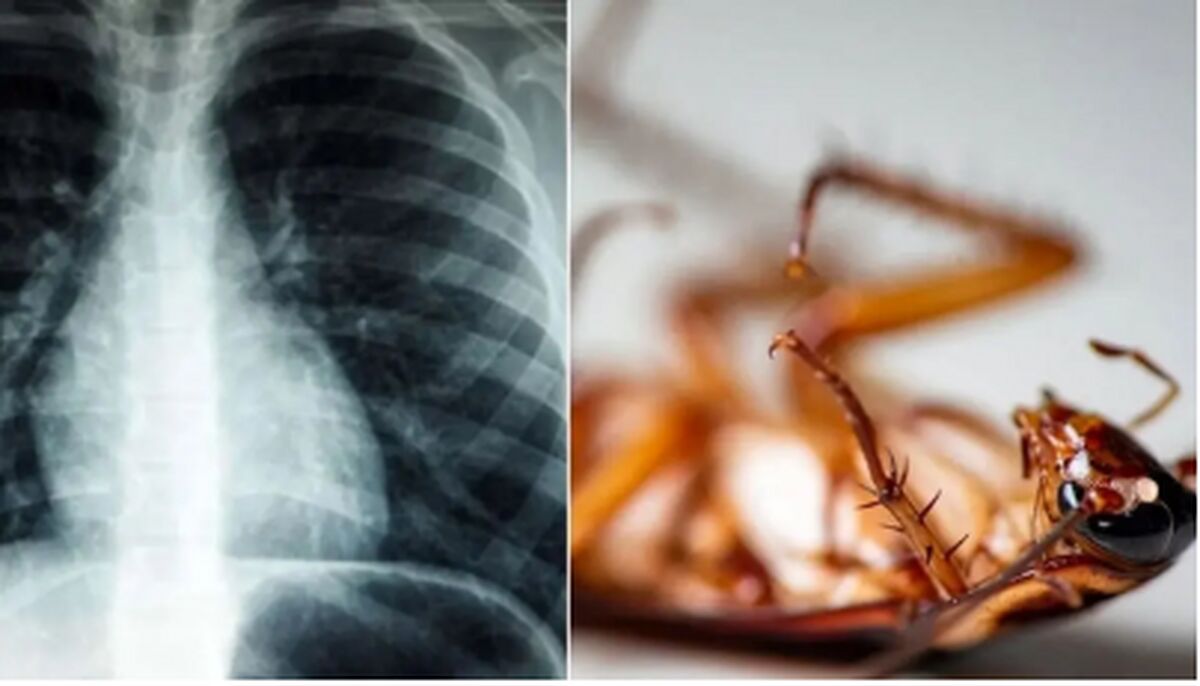

پزشکان اعلام کردند یک سوسک زنده را از داخل ریه یک مرد هندی خارج کردند.

به گزارش سلامت نیوز، اعتماد آنلاین نوشت: به نقل از رسانه‌های عربی، پزشکان در هند، سوسکی چهار سانتی‌متری را از داخل ریه یک بیمار که به دلیل مشکلات تنفسی به بیمارستان مراجعه کرده بود، خارج کردند.

این بیمار ۵۵ ساله به بیمارستان ایالت کرالا مراجعه و اعلام کرد شرایط مناسبی ندارد.

مشکلات تنفسی این فرد باعث شد پزشکان برونکوسکوپی را برایش تجویز کنند تا بدین ترتیب یک سوسک چهار سانتی‌متری در ریه او مشاهده شود.

به گفته پزشکان، ظاهراً سوسک از طریق لوله‌ای که قبلاً در گلوی این مرد برای رساندن اکسیژن ایجاد شده بود، وارد شش او شده است.

به نوشته رسانه‌ها، سوسک بعد از تلاشی چندساعته از ریه بیمار خارج شد.